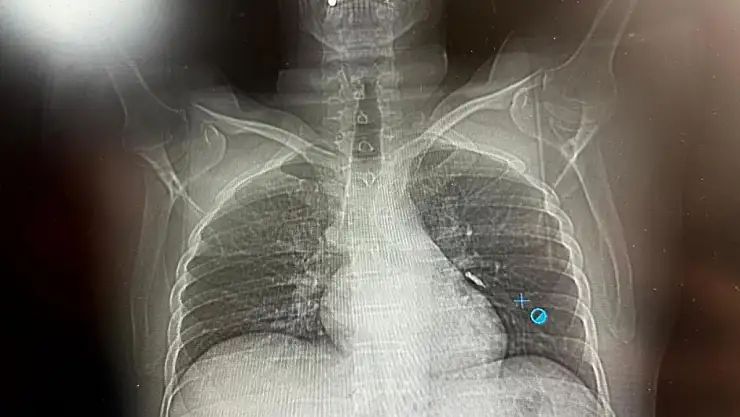

Konuya ilişkin konuşan Göğüs Cerrahi Op. Dr. Sadullah Aksoy, bir diş merkezinde diş tedavisi sırasında hastanın çenesine yerleştirilen implantın vida kısmının işlem esnasında yanlışlıkla aspire edildiğini belirtti. İlk olarak hastanenin ek hizmet binasında çekilen tomografi sonucunda, vidanın sol akciğerin hava yollarının yaklaşık dördüncü dalına kadar ilerlediği tespit edildiğini ifade eden Op. Dr. Aksoy, "Geçtiğimiz cumartesi günü öğle saatlerinde tarafımıza ulaşıldığında, hastanın Van Eğitim ve Araştırma Hastanesi'ne yönlendirilmesini istedik. Burada acil bronkoskopi planı yapılarak hasta kabul edildi. Hasta geldiğinde genel durumu iyiydi; solunumunu tamamen engelleyen bir bronş tıkanıklığı söz konusu değildi. Aynı gün hastamızı hazırladık. Bronkoskopi sırasında, implant vidasının sol üst lobun anterior segment bronşuna saplanmış pozisyonda olduğunu gördük. Üroloji bölümünde taş çıkarma işlemlerinde kullanılan cihazla müdahale ettik. İlk denemede implant tamamen çıkarılamadı ancak yerinden oynatılabildi. Bunun üzerine bir süre bekleyip hastayı yeniden bronkoskopi için hazırlamaya başladık. İşlem yaklaşık 3,5-4 saat sürdü ve saat 18.30 civarında hasta işlemden çıkarıldı" dedi.

Daha sonra hasta için yeniden bronkoskopi planladıklarını ancak bu süreçte hasta şiddetli bir öksürük geçirdiğini anlatan Aksoy, "Şiddetli öksürük sonrası yapılan kontrol akciğer filminde implant vidası görünmedi. Bunun üzerine toraks ve batın BT (bilgisayarlı tomografi) görüntülemesi istedik. Sonuçlarda implantın akciğerden çıktığı ve vücutta herhangi bir yerde bulunmadığı tespit edildi" diye konuştu.